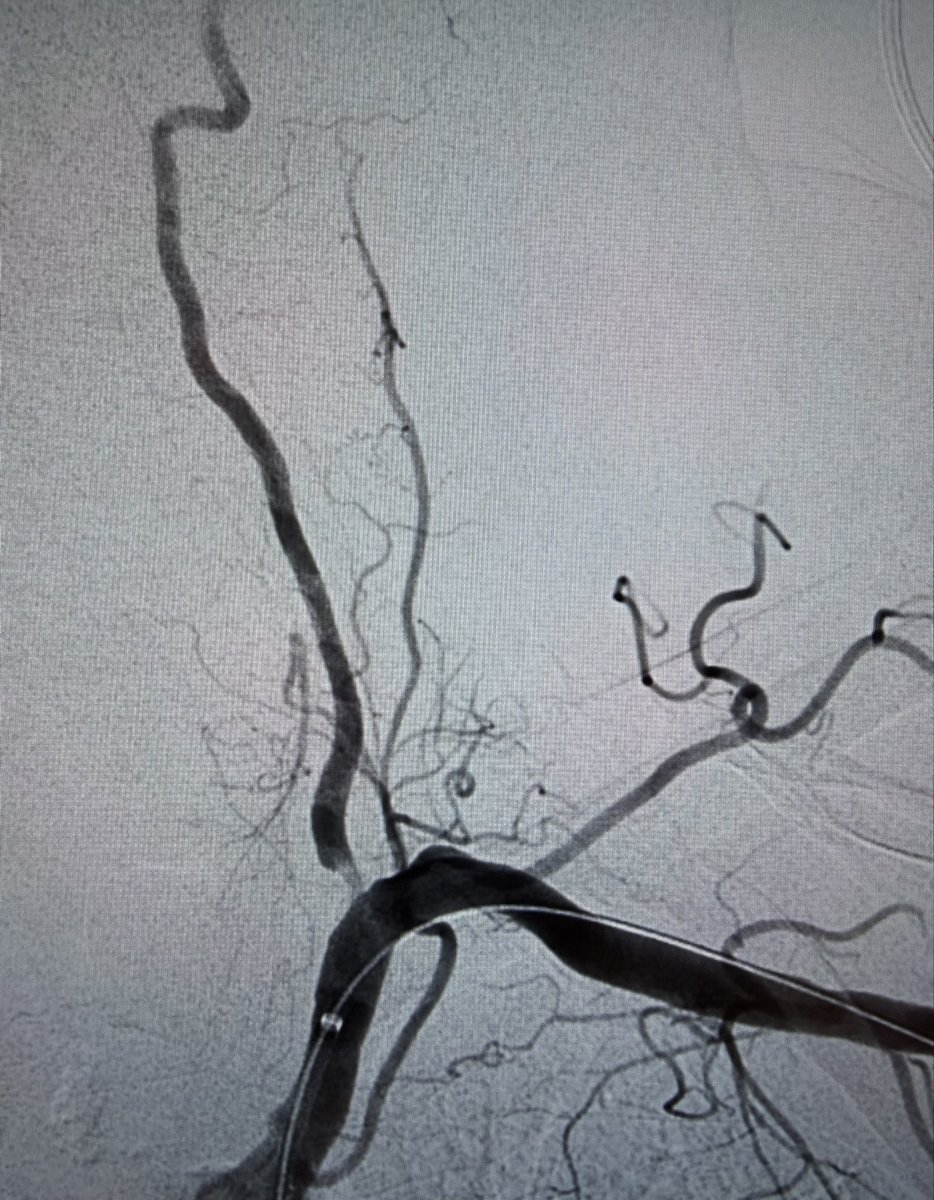

Partial disassembly at the junction to expose the internal stiff wire lets you manually control the lever and free a stuck Perclose footplate—turning a stressful moment into a controlled one. Practical, reproducible, and worth remembering.